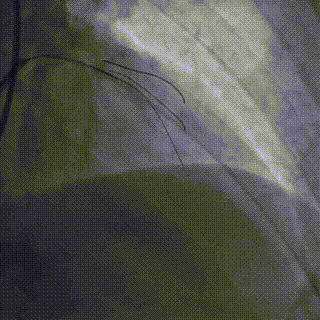

手术影像

LAD、LCX双支 CTO ,LAD 近端50%狭窄

RCA粗大,支架代偿良好。远端60%狭窄,PDA开口80%狭窄

策略讨论:双支CTO,闭塞段残端清晰,钙化,右冠造影可见PLV/PDA侧供LCA。由于有前降支PCI失败史,该次已经做好充分准备,大概率需要逆向PCI。